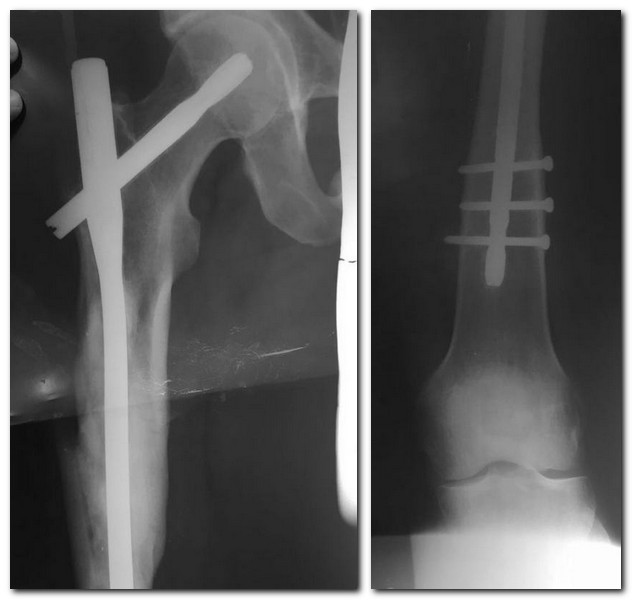

Здравствуйте! Пациент 31 год. Оперирован 3 года назад в другом

учреждении. Штифт Санат

металл.Особенности удаления, послеоперационного ведения.